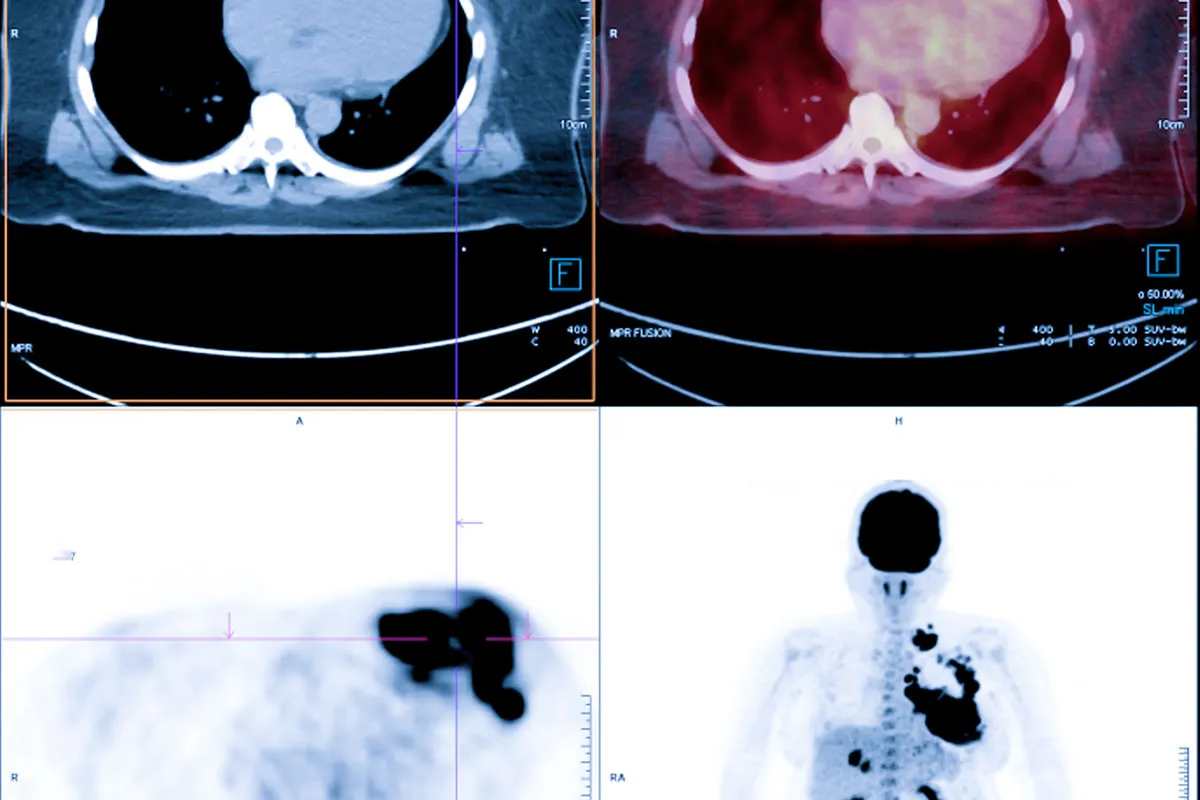

Распространенные Аномалии, Обнаруживаемые при КТ-Сканировании

Компьютерная томография (КТ) помогает выявлять аномалии в разных частях тела. Мы рассмотрим типы аномалий, которые можно обнаружить при КТ-сканировании. Их значение для диагностики и лечения очень важно.

Аномалии Грудной Клетки и Легких

КТ грудной клетки обнаруживает аномалии, такие как:

Опухоли легких и средостения

Пневмония и другие инфекции

Эмболия легочной артерии

Хронические заболевания легких

Эти данные помогают в диагностике и мониторинге заболеваний грудной клетки.